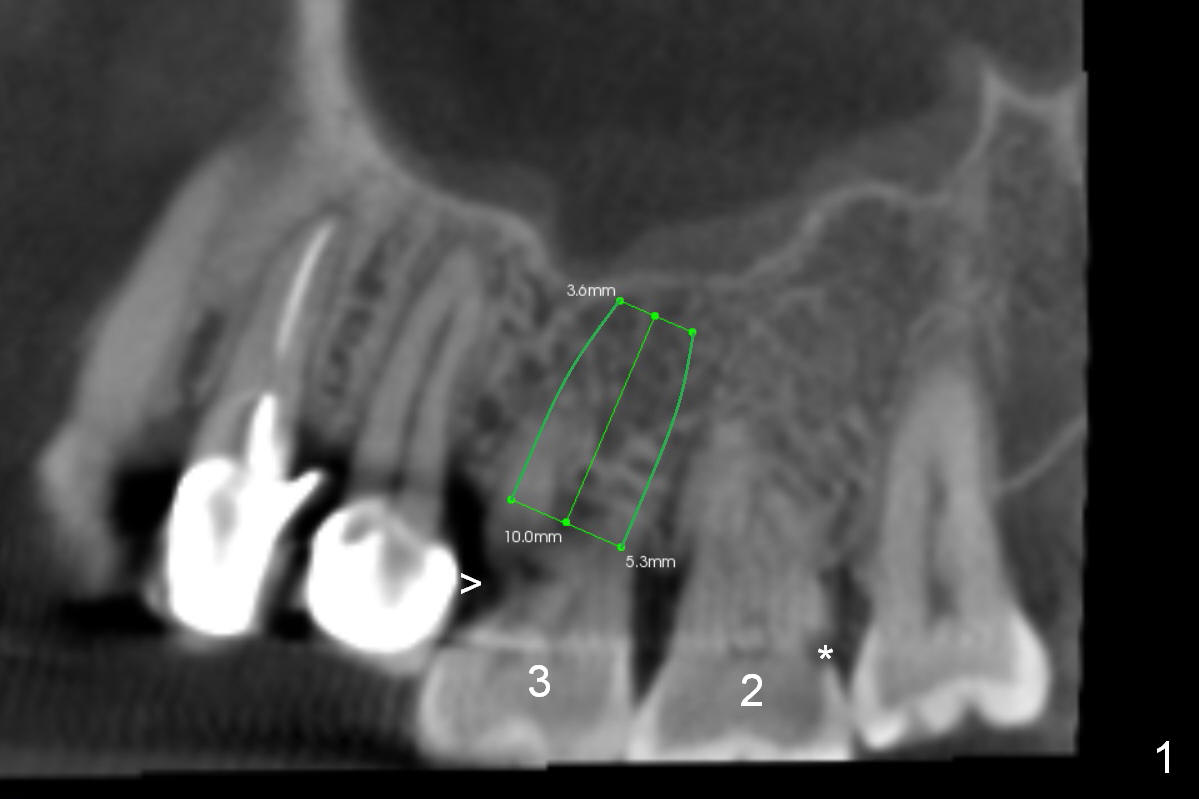

In addition to supraeruption of the teeth #2 and 3, the caries in the mesiobuccal root of #3 seems to be beyond salvation (Fig.1,2 arrowhead). When the implant at #3 is osteointegrated, a provisional restoration is placed (Fig.4 pink). Brackets (white boxes) are placed at differential levels among #1-3 to initiate regional orthodontic treatment using #3 as an anchorage. Mini-implants are placed if necessary. The tooth #1 is extracted after the limited ortho. Scaling & root planing will be done first.

Re-examination clinically and radiologically reveals that there is no caries involving the tooth #3 (Fig.5). It appears that CBCT may have artifact. Treatment planning for intrusion should be modified. Mini-implants will be employed after #2 DO composite. Prepare Anchor mini-implant kit, 2 of 10 mm and 1 of 8 mm mini-implants, anesthetics and #15 scalpel. Scaling & root planing will be performed.